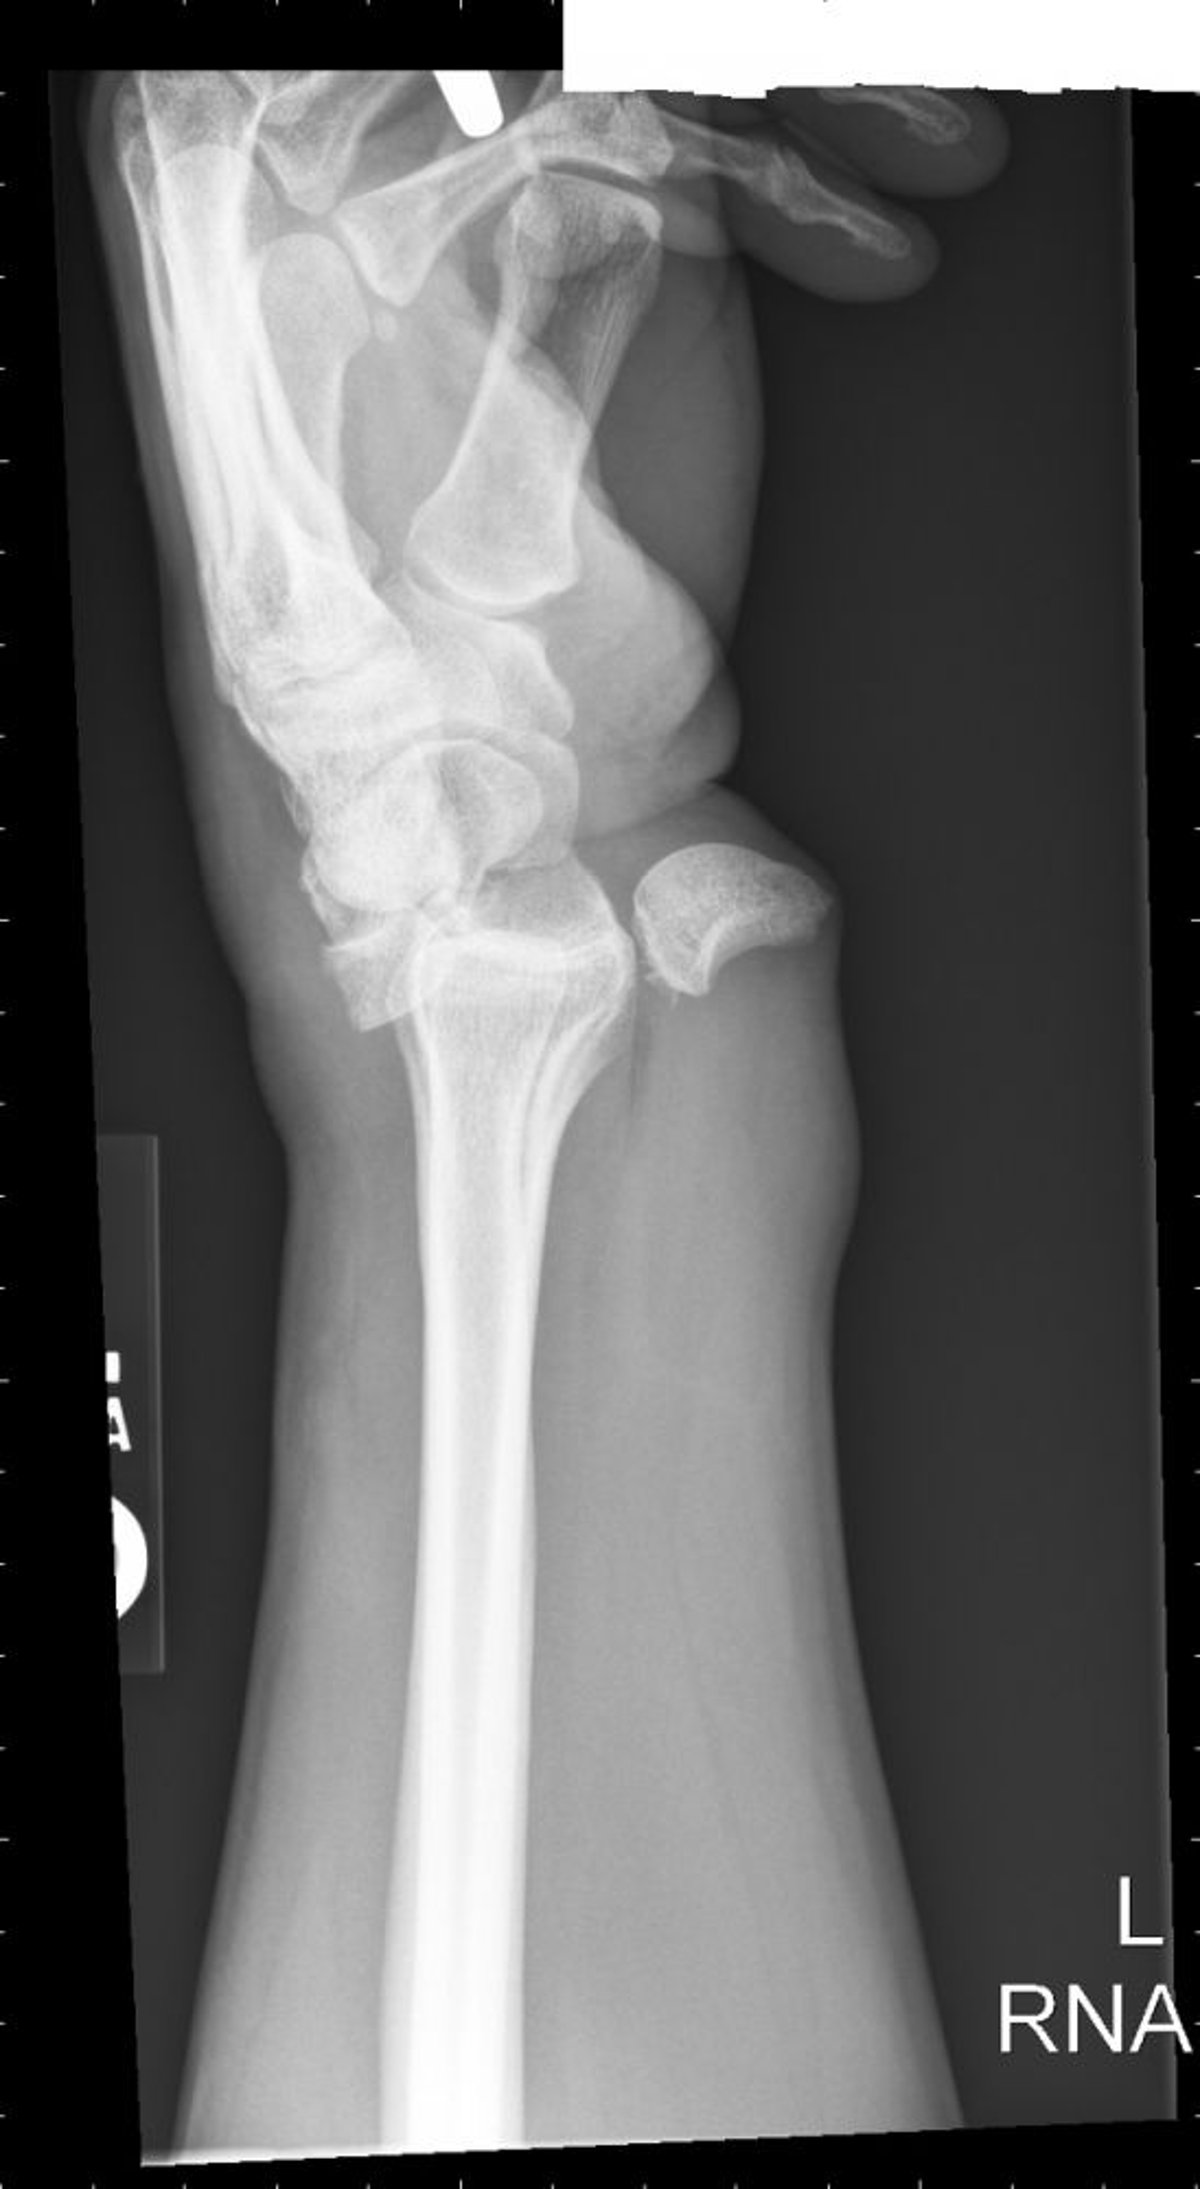

Лунарний вивих

Вивих півмісяцевої кістки призводить до конфігурації розлитої чашки, де півмісяцева кістка обертається і зміщується волярно.

Знімок люб'язно надано лікарем Даніелем Кампаньє [Danielle Campagne], MD.